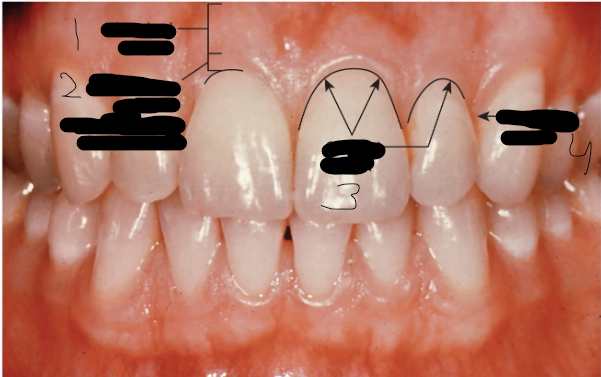

Gingiva adherens, Aangehechte gingiva, Attached gingiva (Afbeelding)(Parodontium, kliniek)

1

Gingiva libera (over the mogelijke ruimte: sulcus gingivalis), Vrije gingiva, Free gingiva (Afbeelding)(Parodontium, kliniek)

2

Margo gingivalis, Tandvleesrand, Gingival margin (Afbeelding)(Parodontium, kliniek)

3

Papilla interdentalis, Interdentale papil, Interdental papilla (Afbeelding)(Parodontium, kliniek)

4